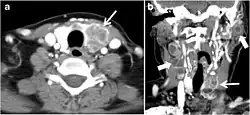

Fig. 7. A 51-year-old female patient post total thyroidectomy for PTC with elevated thyroglobulin measurement. an Axial non-enhanced CT scan of the neck at the level of the thyroid bed demonstrates a well-defined, rounded, homogenously dense soft tissue situated between the trachea and left internal jugular vein (white arrow). b Transverse ultrasound image of the neck demonstrates a well-defined, homogeneous, hypoechoic soft tissue nodule measuring 6 mm (white arrow) with no detected micro-calcifications. Biopsy showed a predominantly residual normal thyroid tissue with micro-foci of PTC.[1] -

The likelihood of positive anatomic imaging is greater when serum Tg is >10 ng/mL. A diagnostic CT scan adds additional value to neck US in detecting central compartment macro-metastases in the mediastinum and retro-tracheal area. According to the recent American Thyroid Association guidelines, an upper chest and neck CT scan with IV contrast should be obtained when: 1) neck US is inadequate in visualizing possible local nodal disease (high Tg, negative neck US, and RAI imaging); 2) US is not able to delineate the disease completely, as in the case of bulky recurrent nodal disease; or 3) evaluation of possible recurrent invasive disease is needed (Figs. 7, 88 and and9).9). CT scans are also the most sensitive diagnostic tool for the detection of pulmonary micro-metastases. Many of the neck US features that are considered as suggestive signs of disease recurrence are also applicable to CT examination. These signs might include sizable rounded nodules in the thyroid bed, fine calcifications, or cystic change.[1]